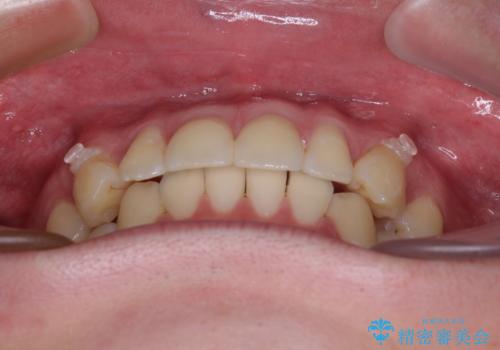

- 前歯のデコボコと突出感を気にして来院された患者様です。

極力目立たない装置を希望とのことで、インビザラインを用いて非抜歯で矯正治療を行うこととしました。

事前に親知らず4本を抜歯し、多少歯列を後方に移動できるように準備をした上で、なるべく歯と歯の間を削ることなくデコボコを解消できるように計画しました。

お仕事が忙しく、1日の装着時間は不十分となる日もありましたが、治療は順調に進めていくことができました。

途中、以前大きなむし歯で処置をした歯が痛み出し、根管治療が必要となったため、根管治療とオールセラミッククラウンによる補綴治療を行い、その後にインビザラインによる仕上げの歯列移動を行い、無事に治療を終えることができました。